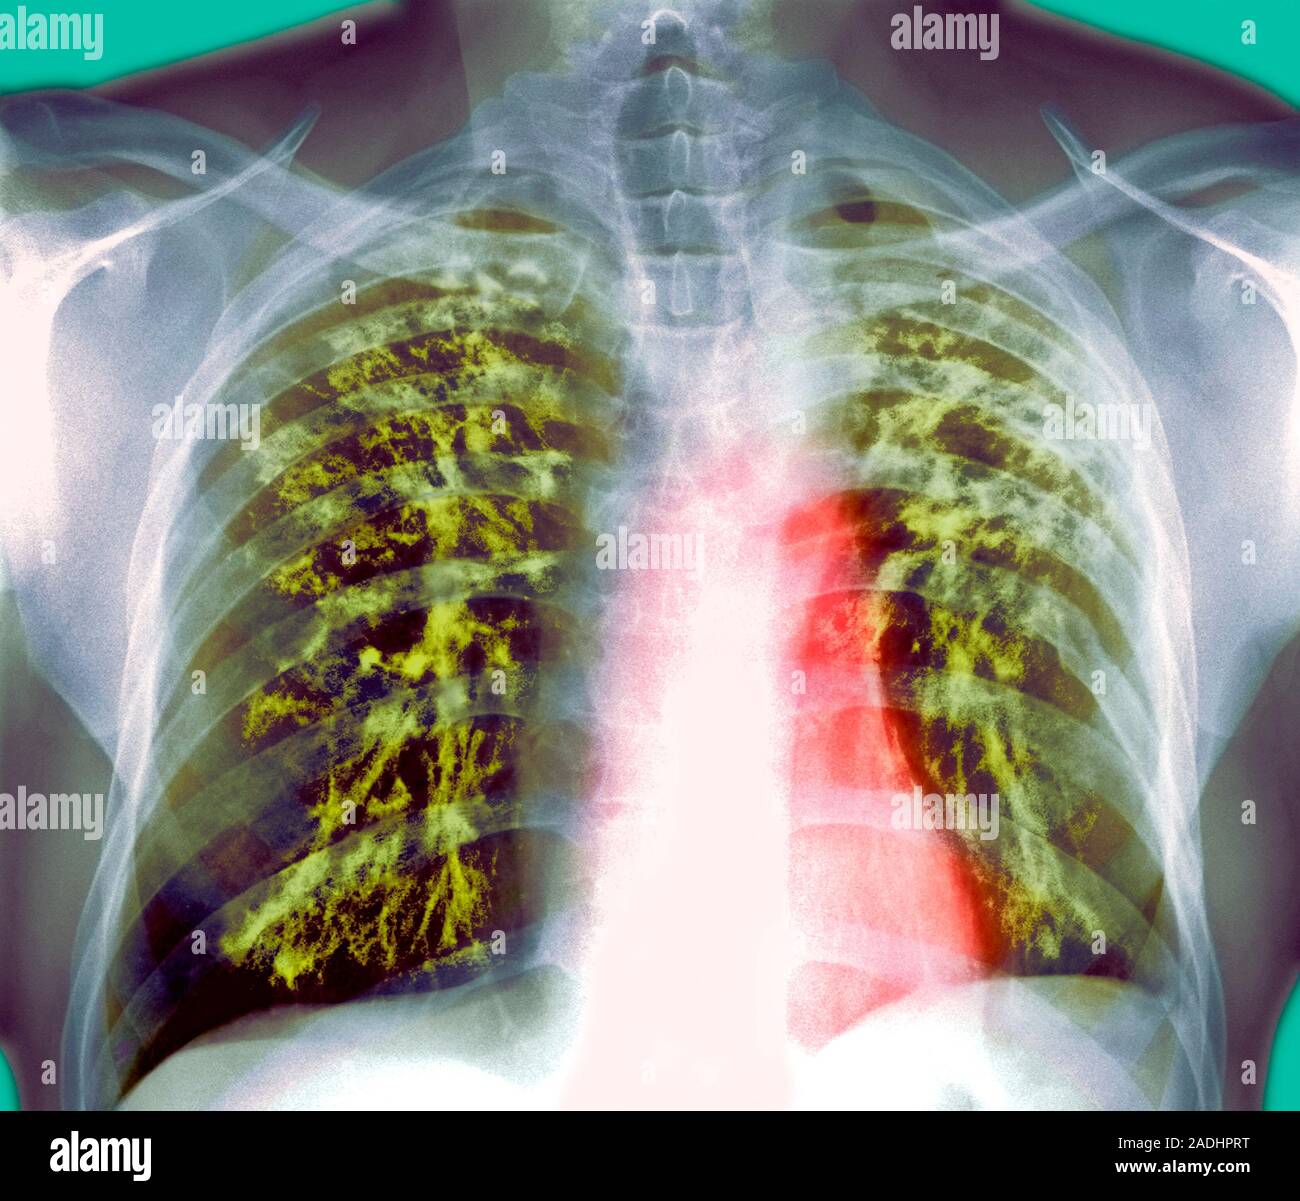

Снимок легких при туберкулезе является важным методом диагностики этого заболевания. На рентгеновских снимках можно увидеть изменения в легких, которые свойственны туберкулезу.

Очаговый туберкулез рентген

Рентген грудной клетки туберкулез

Фотографии снимков легких при туберкулезе

В данной статье представлены многочисленные фотографии снимков легких при туберкулезе, чтобы помочь вам понять, как выглядят изменения легких на рентгеновских снимках при этом заболевании.